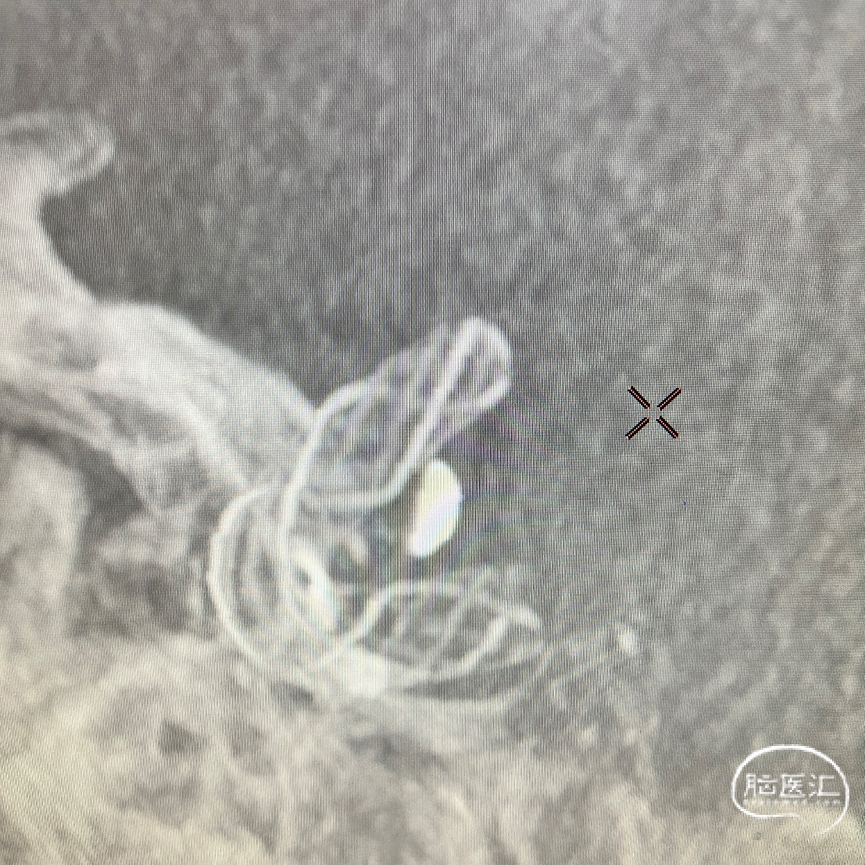

术后DSA即刻造影见Nuva®血流导向密网支架远近端均定位准确,贴壁良好。

末次DSA造影显示:各分支充盈良好;复查CT未见明显梗塞。

【密网支架贴壁良好】